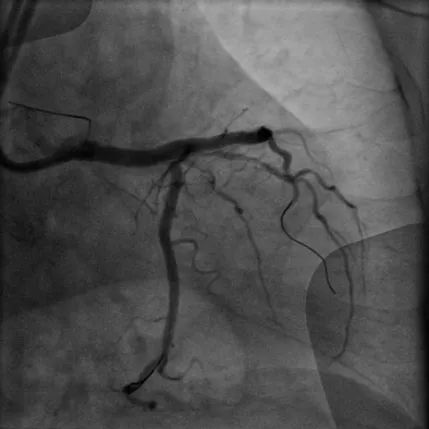

病例1

LAD长弥漫钙化病变:患者70岁男性,因间断胸痛3天入院,既往高血压病史、长期吸烟史,诊断不稳定型心绞痛。冠脉造影显示前降支近中段弥漫性狭窄伴钙化,应用冠脉腔内影像学技术-IVUS对该血管进一步评估,结果显示:前降支多处180-270°钙化,中段钙化结节(红色箭头所示)。顺利送入3.0*12mm Shockwave冲击波球囊至LAD中段,充盈4atm使球囊充分贴壁,显示球囊近段膨胀不良,随着冲击波能量释放,球囊逐渐扩张,膨胀扩张满意。先后对LAD多处钙化病变进行8个周期(80次脉冲)预处理,应用IVUS评估显示钙化处出现钙化断裂。该患者多处弥漫钙化病变,在IVUS指导下联合Shockwave冲击波球囊实现精准预处理,为后续支架植入奠定了基础。果然,送入长支架通过病变顺畅,释放扩张未感觉明显阻力即到位,支架膨胀舒展,成功植入支架。IVUS结果显示支架膨胀贴壁良好。

术前冠脉造影